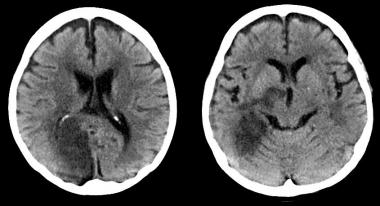

En un subestudio del SPRINT se encuentra que los niveles más bajos de presión arterial se asociaron a una pequeña disminución de lesiones de la sustancia blanca, de significación clínica incierta. JAMA 13 de agosto de 2019